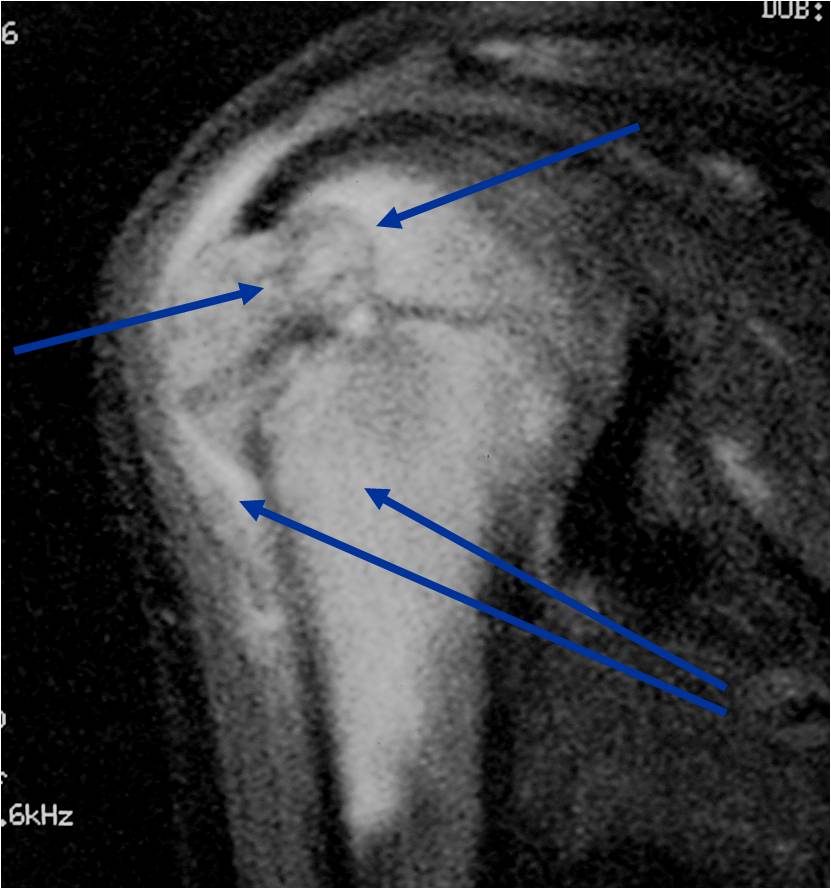

General Information Enchondroma is a benign indolent intramedullary hyaline cartilage neoplasm Accounts for 10% of all benign osseous tumors Limited growth, most lesions are less than 5 cm in maximal dimension Bones grow from a cartilaginous growth plate that...